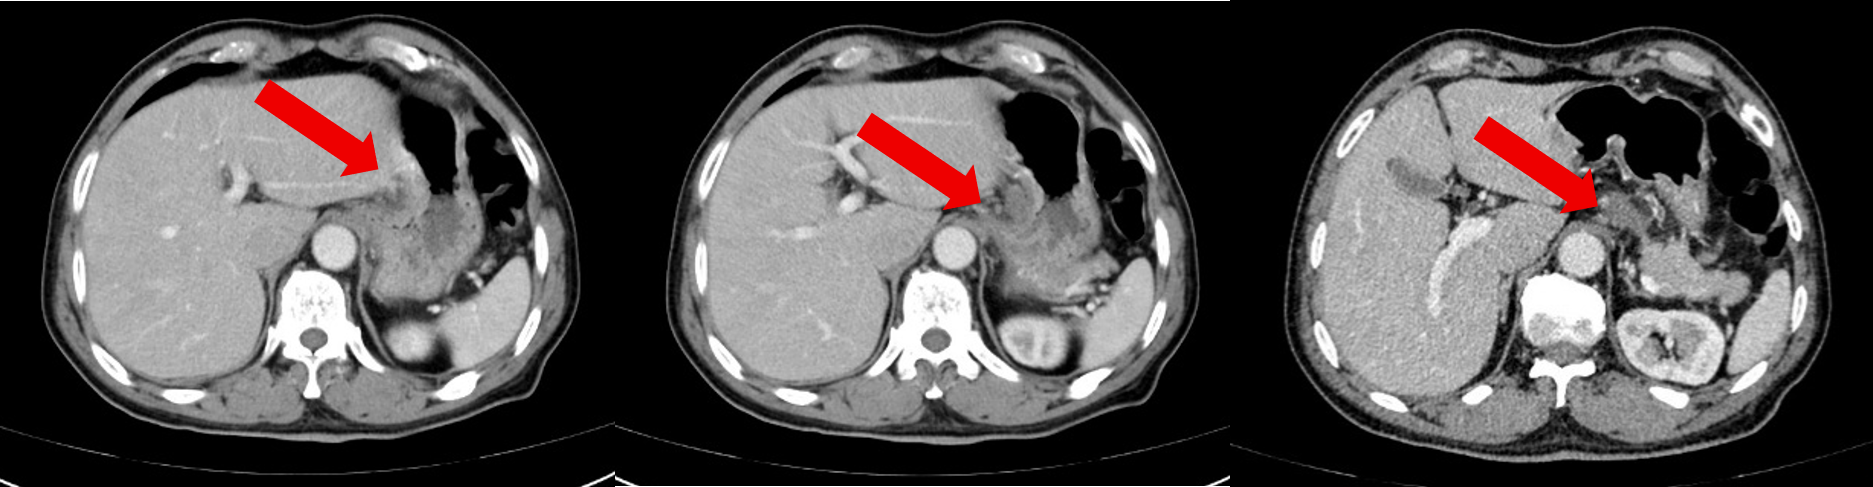

治疗4周期后患者于2024-12-27复查腹部CT:胃底、胃体小弯侧胃壁不均增厚,与邻近贲门分界不清,较前大致类似,病灶较厚处约1.3cm。贲门左、胃小弯及肝胃间隙数个增大淋巴结,多系转移,多数较前缩小,大者大小约2.6×1.6cm。

治疗6周期后患者于2025-3-6复查腹部CT:胃底、胃体小弯侧胃壁不均增厚,与邻近贲门分界不清,较前大致类似,病灶较厚处约 1.3cm。贲门左、胃小弯及肝胃间隙数个增大淋巴结,多系转移,部分较前稍缩小,大者大小约2.6×1.5cm。